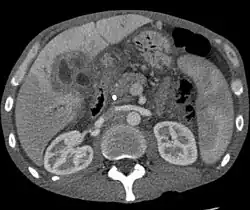

![]() Rak dróg żółciowych w obrębie wątroby |

- Tomografia komputerowa (TK)

Tomografia komputerowa może wykazać poszerzenie dróg żółciowych i masę nowotworową, pogrubienie ścian przewodu żółciowego lub wewnątrzprzewodową masę nowotworową[85]. Przed podaniem środka kontrastującego guz jest bardzo słabo widoczny. Guz jest słabo unaczyniony, dlatego nie ulega wzmocnieniu kontrastowemu, ale jest lepiej widoczny na tle dobrze unaczynionej wątroby[84]. Tomografia komputerowa służy do oceny zaawansowania choroby oraz operacyjności choroby, w tym do oceny zajęcia lokalnych węzłów chłonnych, obecności przerzutów odległych oraz zajęcia ważnych naczyń krwionośnych[84].